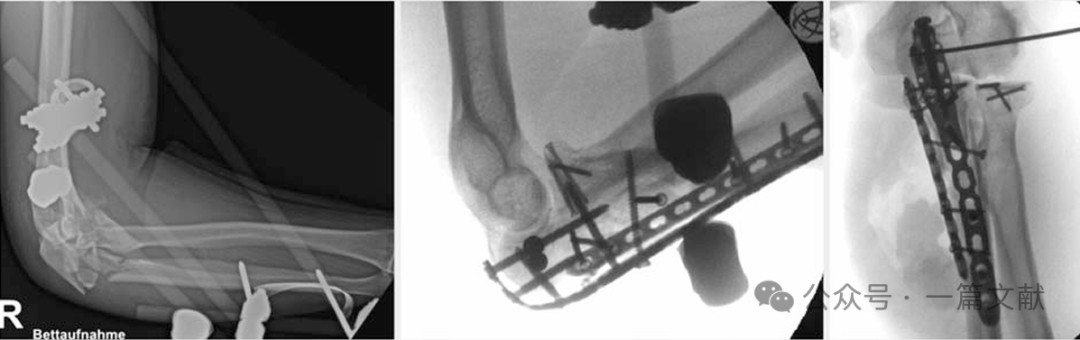

如下图:55岁患者,患有类似Monteggia损伤:左图:尺骨近端粉碎性骨折,初期采用外固定架进行固定。中图和右图:桡骨头螺钉固定,以及尺骨近端双钢板固定(背侧和尺侧LCP)。

下图:26岁女性铁人三项运动员,鹰嘴骨折Mayo 2b型:左上图:术前显示鹰嘴骨折。右上图:术中首先对关节面进行复位,并使用克氏针暂时固定。下图:随后采用双钢板固定骨折。